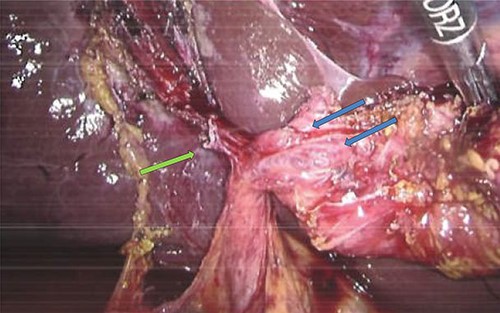

Perioperatively, retrograde dissection of gallbladder was performed due to gallbladder being thick, fibrotic, intrahepatic and access to Calot’s triangle was obscured by dense omental adhesions. Gallbladder was opened at Hartman’s pouch to perform an intraoperative cholangiogram safely; two bile-flowing tube structures were found at base of Hartman’s (Fig. 1). Intraoperative cholangiogram catheter was only able to be performed via one of the two ducts with no evidence of leak (Fig. 2). A Hepatobiliary Surgeon was consulted intraoperatively, the decision was to complete a subtotal cholecystectomy with the stump, containing both lumens, secured with Endoloop ties. 15F Blakes drain was placed at the gallbladder bed.

Intraoperative image showing gallbladder with two duct structures (blue arrows); cystic artery clipped on left (green arrow).